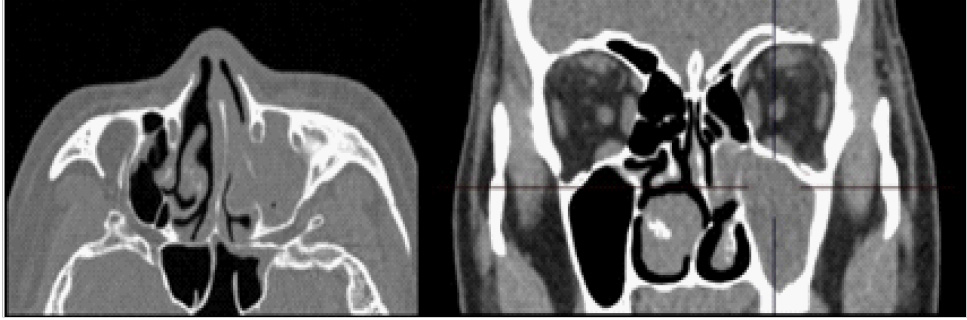

На компьютерной томограмме в передней камере глаза отмечалась структура диаметром 3,7 мм, металлической плотности до 3000 HU (Hounsfield Units) (рис. 4).

Рис. 4. Компьютерная томограмма области орбиты. ВГИТ указано стрелкой, хрусталик на глазном дне – наконечником стрелки

В заднем сегменте глазного яблока отмечалась дополнительная структура диаметром 8,5 мм, плотность 92 HU. В области сканирования левая верхнечелюстная пазуха тотально заполнена содержимым, ячейки решетчатой кости с субтотальным заполнением просвета (рис. 5).

Рис. 5. Компьютерная томограмма области околоносовых пазух